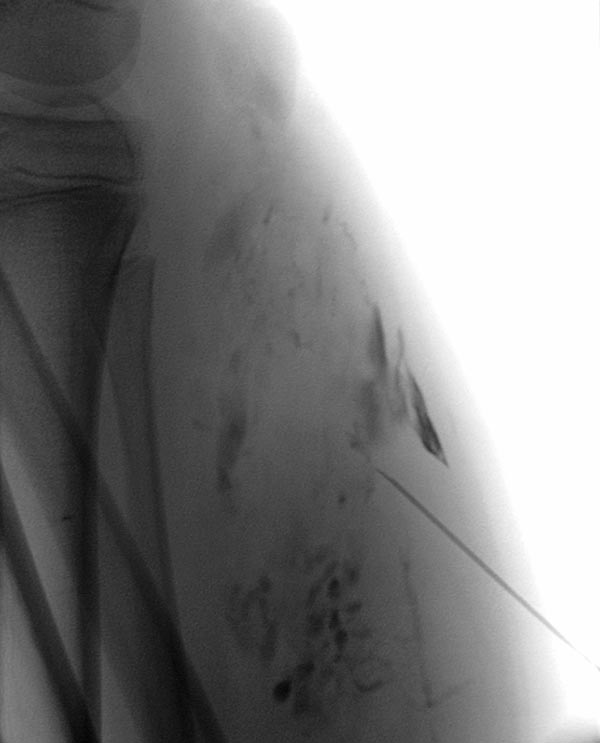

Die Phlebographie nach Direktpunktion des venösen Malformationsanteils zeigt eine großlumige Drainagevene, die in der Kniekehle mit der V. poplitea kommuniziert. Diese muss zunächst verschlossen werden, da sonst das Sklerosierungsmittel darüber abfließen könnte und potentiell eine Thrombose der tiefen Leitvenen des Beins (und eine Lungenembolie) verursachen könnte. Zudem besteht grundsätzlich ein erhöhtes Thrombembolierisiko bei der Patientin, dass durch den Verschluss deutlich vermindert werden kann.

Dazu wird zunächst über einen Einführungsdraht eine großlumige Einführungsschleuse vorgebracht, die zum Einführen der Laserfaser dient. Dieser wird über die Vene bis zum Kommunikationspunkt in der Kniekehle vorgeschoben.